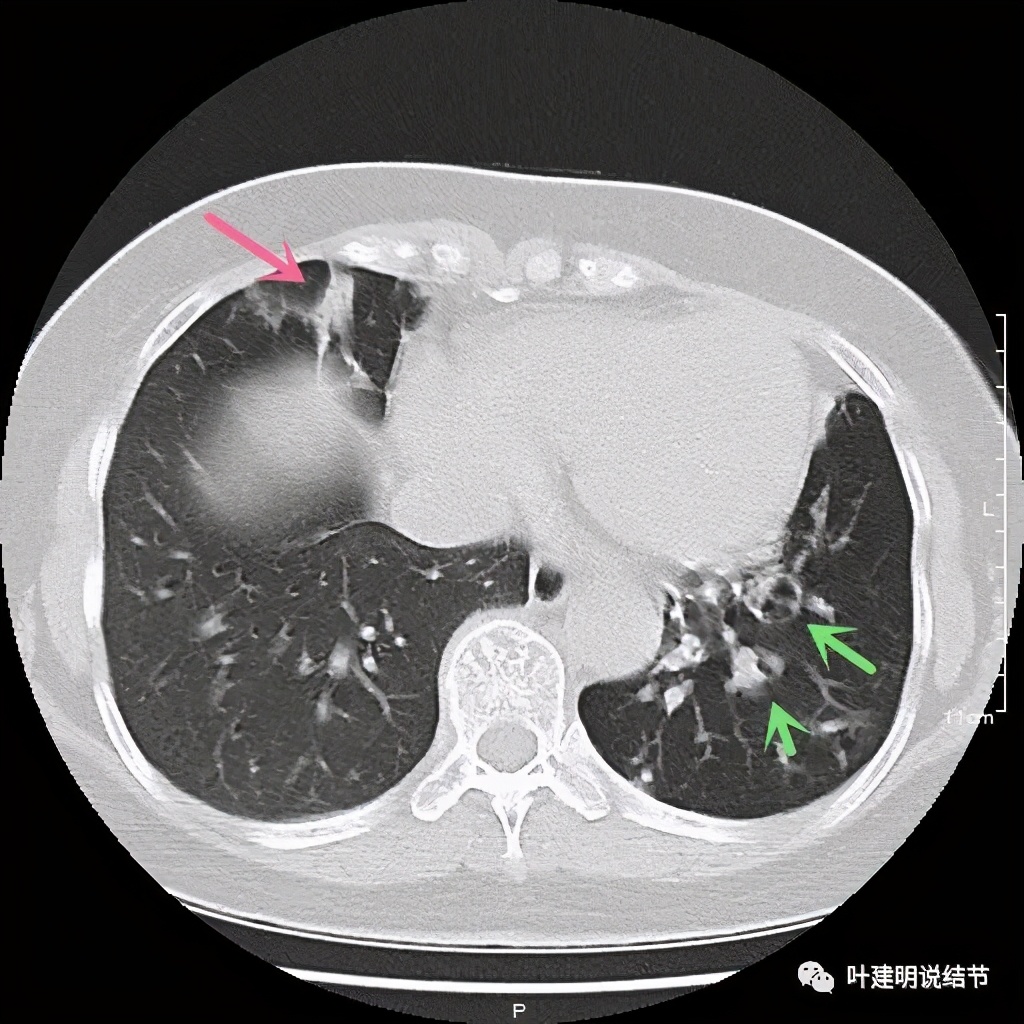

上图见病灶为实性,中间有小空洞,边上有血管进入病灶,靠后侧有棘突样

上图示病灶边缘不光滑,中间有小空洞

上图见病灶边上有血管

上图示病灶血管征较明显,有微小血管从不同方向走向病灶